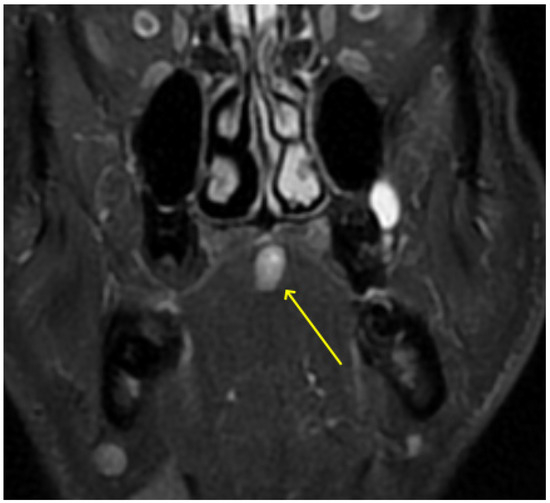

2. Detailed Case Description